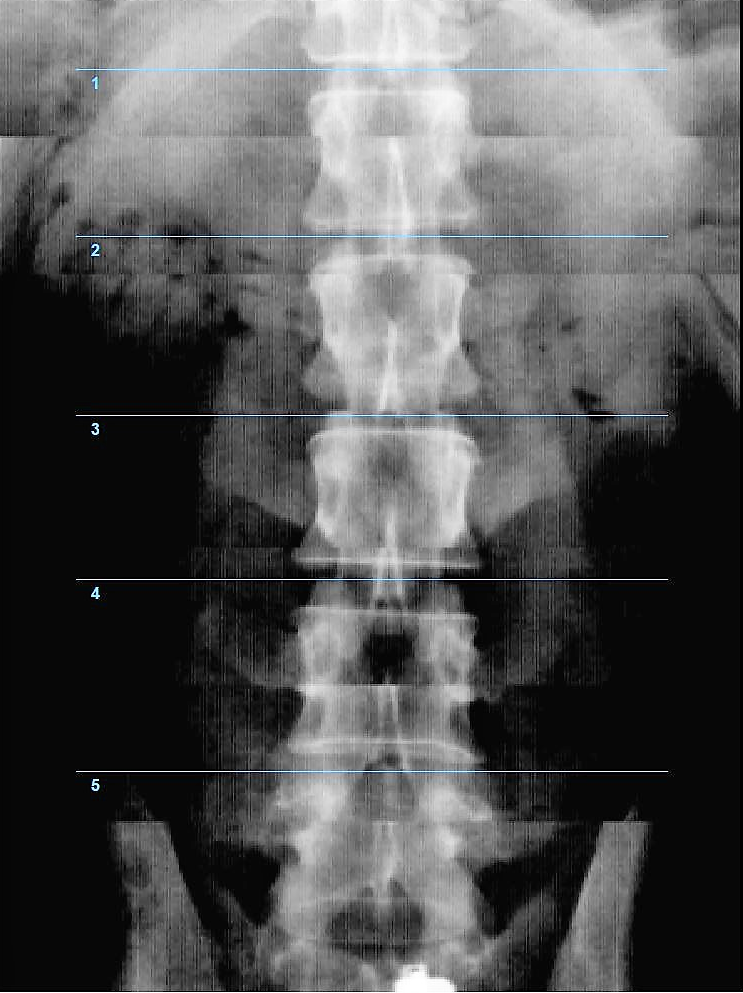

Денситометр InAlyzer-AIR, разработанный компанией Medikors, использует технологию рентгеновского излучения. Он пропускает сфокусированный рентгеновский луч через анализируемый объект – кость. Измеряется степень поглощения рентгеновских лучей, и эта информация используется для расчёта плотности и состава. Эта технология позволяет неинвазивно измерять минеральную плотность костной ткани и может использоваться для точной и достоверной диагностики остеопороза или мониторинга эффективности лечения.

- Диагностика и профилактика. Проведение скрининговых исследований при заболеваниях, сопровождающихся снижением минеральной плотности костной ткани.

- Ревматология. Эндокринология. Травматология. Диагностика и лечение остеопороза.

- Гинекология. Снижение минеральной плотности костной ткани может происходить на фоне менопаузы, женщины в этом возрасте находятся в группе риска остеопороза, поэтому важно контролировать состояние их костей и суставов.

- Педиатрия. Определение минеральной плотности костей помогает контролировать формирование и развитие скелета у детей.